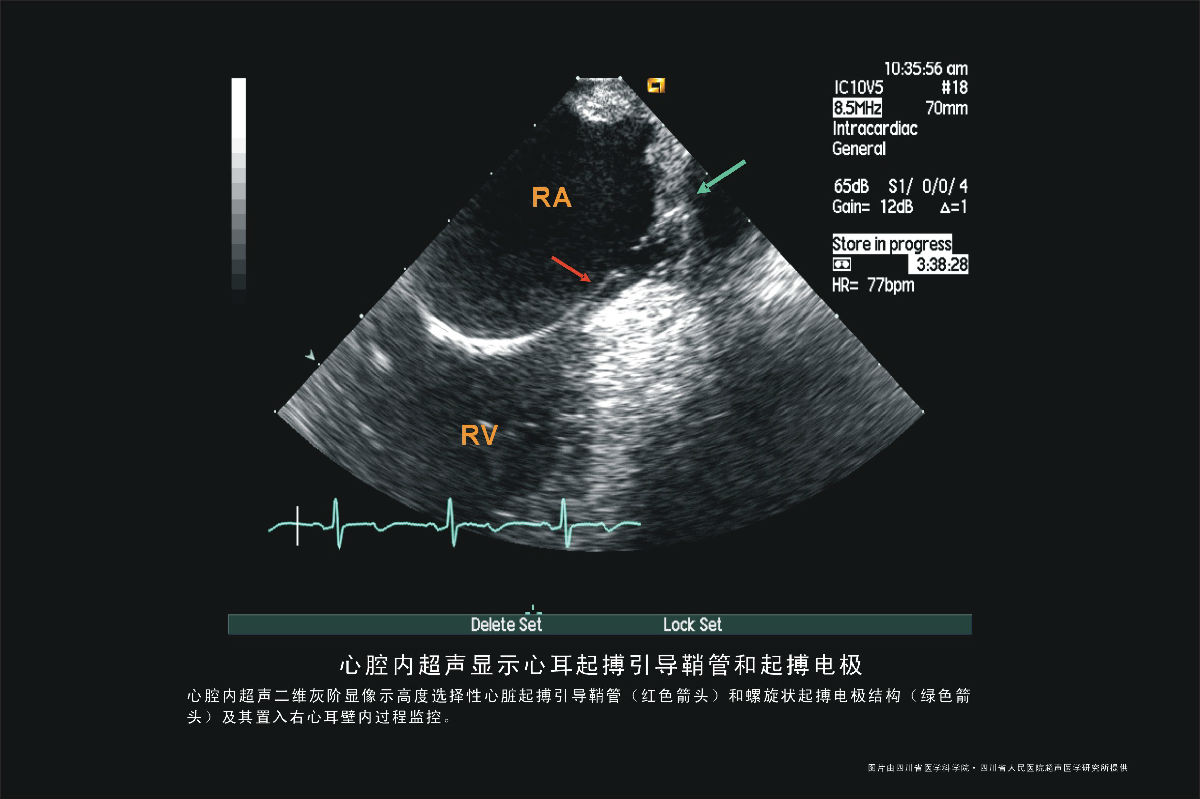

心耳起搏